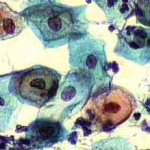

Η κυτταρολογικές εικόνες του έρπητα του τραχήλου της μήτρας, παρουσιάζουν πάντοτε ενδιαφέρον, επειδή οι αλλοιώσεις που προκαλεί είναι πολλαπλές και μπορεί να προβληματίσουν τον εξεταστή.

Ασυμπτωματική σθενής 23 ετών. Κολποσκοπικως κφ. Δοκιμασίες οξικου οξέως και lugol αρνητικές. Ακολουθούν εικόνες του έτους 2000: Kύτταρα κυρίως της επιφ. καi διαμέσου στιβάδος, κάπως μικρότερα απ' ότι συνηθως, με αρραιοχρωματικους φυσαλιδοειδείς πυρήνες . Πολλά απο αυτά με διακριτική κοιλοκυττάρωση και εκφυλυστικές αλλοιώσεις του πυρήνα. Επίσης αρκετά γιγαντιοκύτταρα και εκφυλιστικές αλλοιώσεις πυρήνων με διάλυση και εν μέρει ομοιογενοποίηση της χρωματίνης, που δίνουν την εικόνα θολού γιαλιού. (Mattglasphaenomen). Aρραιή βακτ. χλωριδα. Λιγα πολυμορφοπύρηνα. Aρνητικό για κακοήθεια. Aλλοιώσεις που συνηγορούν για HSV.

Οι αλλοιώσεις συνέχισαν να υπάρχουν 3 και 6 μήνες αργότερα. Μετά επί 18 μήνες και μέχρι σήμερα (Οκτ. 2002), τα επιχρίσματα που πήραμε ανα 6μηνο, ήταν τελείως φυσιολογικά.